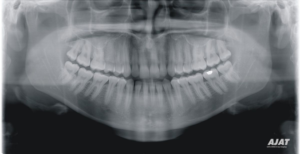

I naše ordinace nabízí vysoce kvalitní panoramatický rentgen, osvědčený model Ajat ART Plus. Tento přístroj díky své multifokální technologii a vysoce kvalitnímu CdTe senzoru umožňuje zhotovit OPG snímky s unikátním rozlišením. Patří mezi rentgeny na trhu, které kombinují CdTe-CMOS technologii (revoluční patentovaná technologie s přímou konverzí rtg záření na elektrický signál, výsledkem je: 3x vyšší citlivost senzoru, 3x lepší kvalita zobrazení, vysoký dynamický rozsah snímku) s technologií multifokální. Panoramatický snímek je tedy s 3x krát lepší kvalitou než u mnohých jiných panoramatických rentgenů navíc s možností posunu fokální vrstvy po projekci s přesným zaostřením na všechny úseky maxilárního a mandibulární oblouku. Výsledkem je vyjímečně ostrý snímek ve všech úsecích.

zdroj: ajat.fi